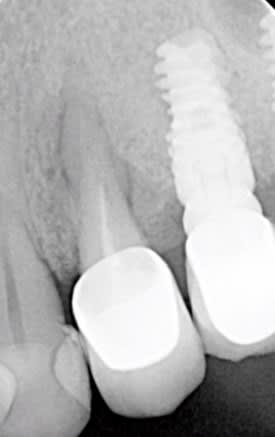

Que pensez vous du pronostic de cette 24.

A l'examen endobuccal, présence d'une fistule vestibulaire et mobilité

Diagnostic: Parodontite apicale aigue fistulisée + Résorption radiculaire inflammatoire latérale.

La racine a l'air courte...

C'est pas un bon pronostic du tout.

Le rapport C/R est trop juste, et la racine trop frêle.

implant directement

quant à la résorption radiculaire externe je n'en suis pas aussi certain que toi, ça mériterait une autre petite radio

si il y a une résorption certains la traitent au MTA + obturation, mais bon dans ce cas je pense qu'une extraction +pose d' implant ne serait pas une mauvaise idée.

si il n'y a pas de résorption : déposer la couronne + traitement endo

C est une 14 donc 2 canaux a traiter d ailleurs l endo devrait etre facilement ameliorable a condition que ca en vaille le coup

Quand on voit la tronche de l'implant....on se demande comment la radio a été prise....